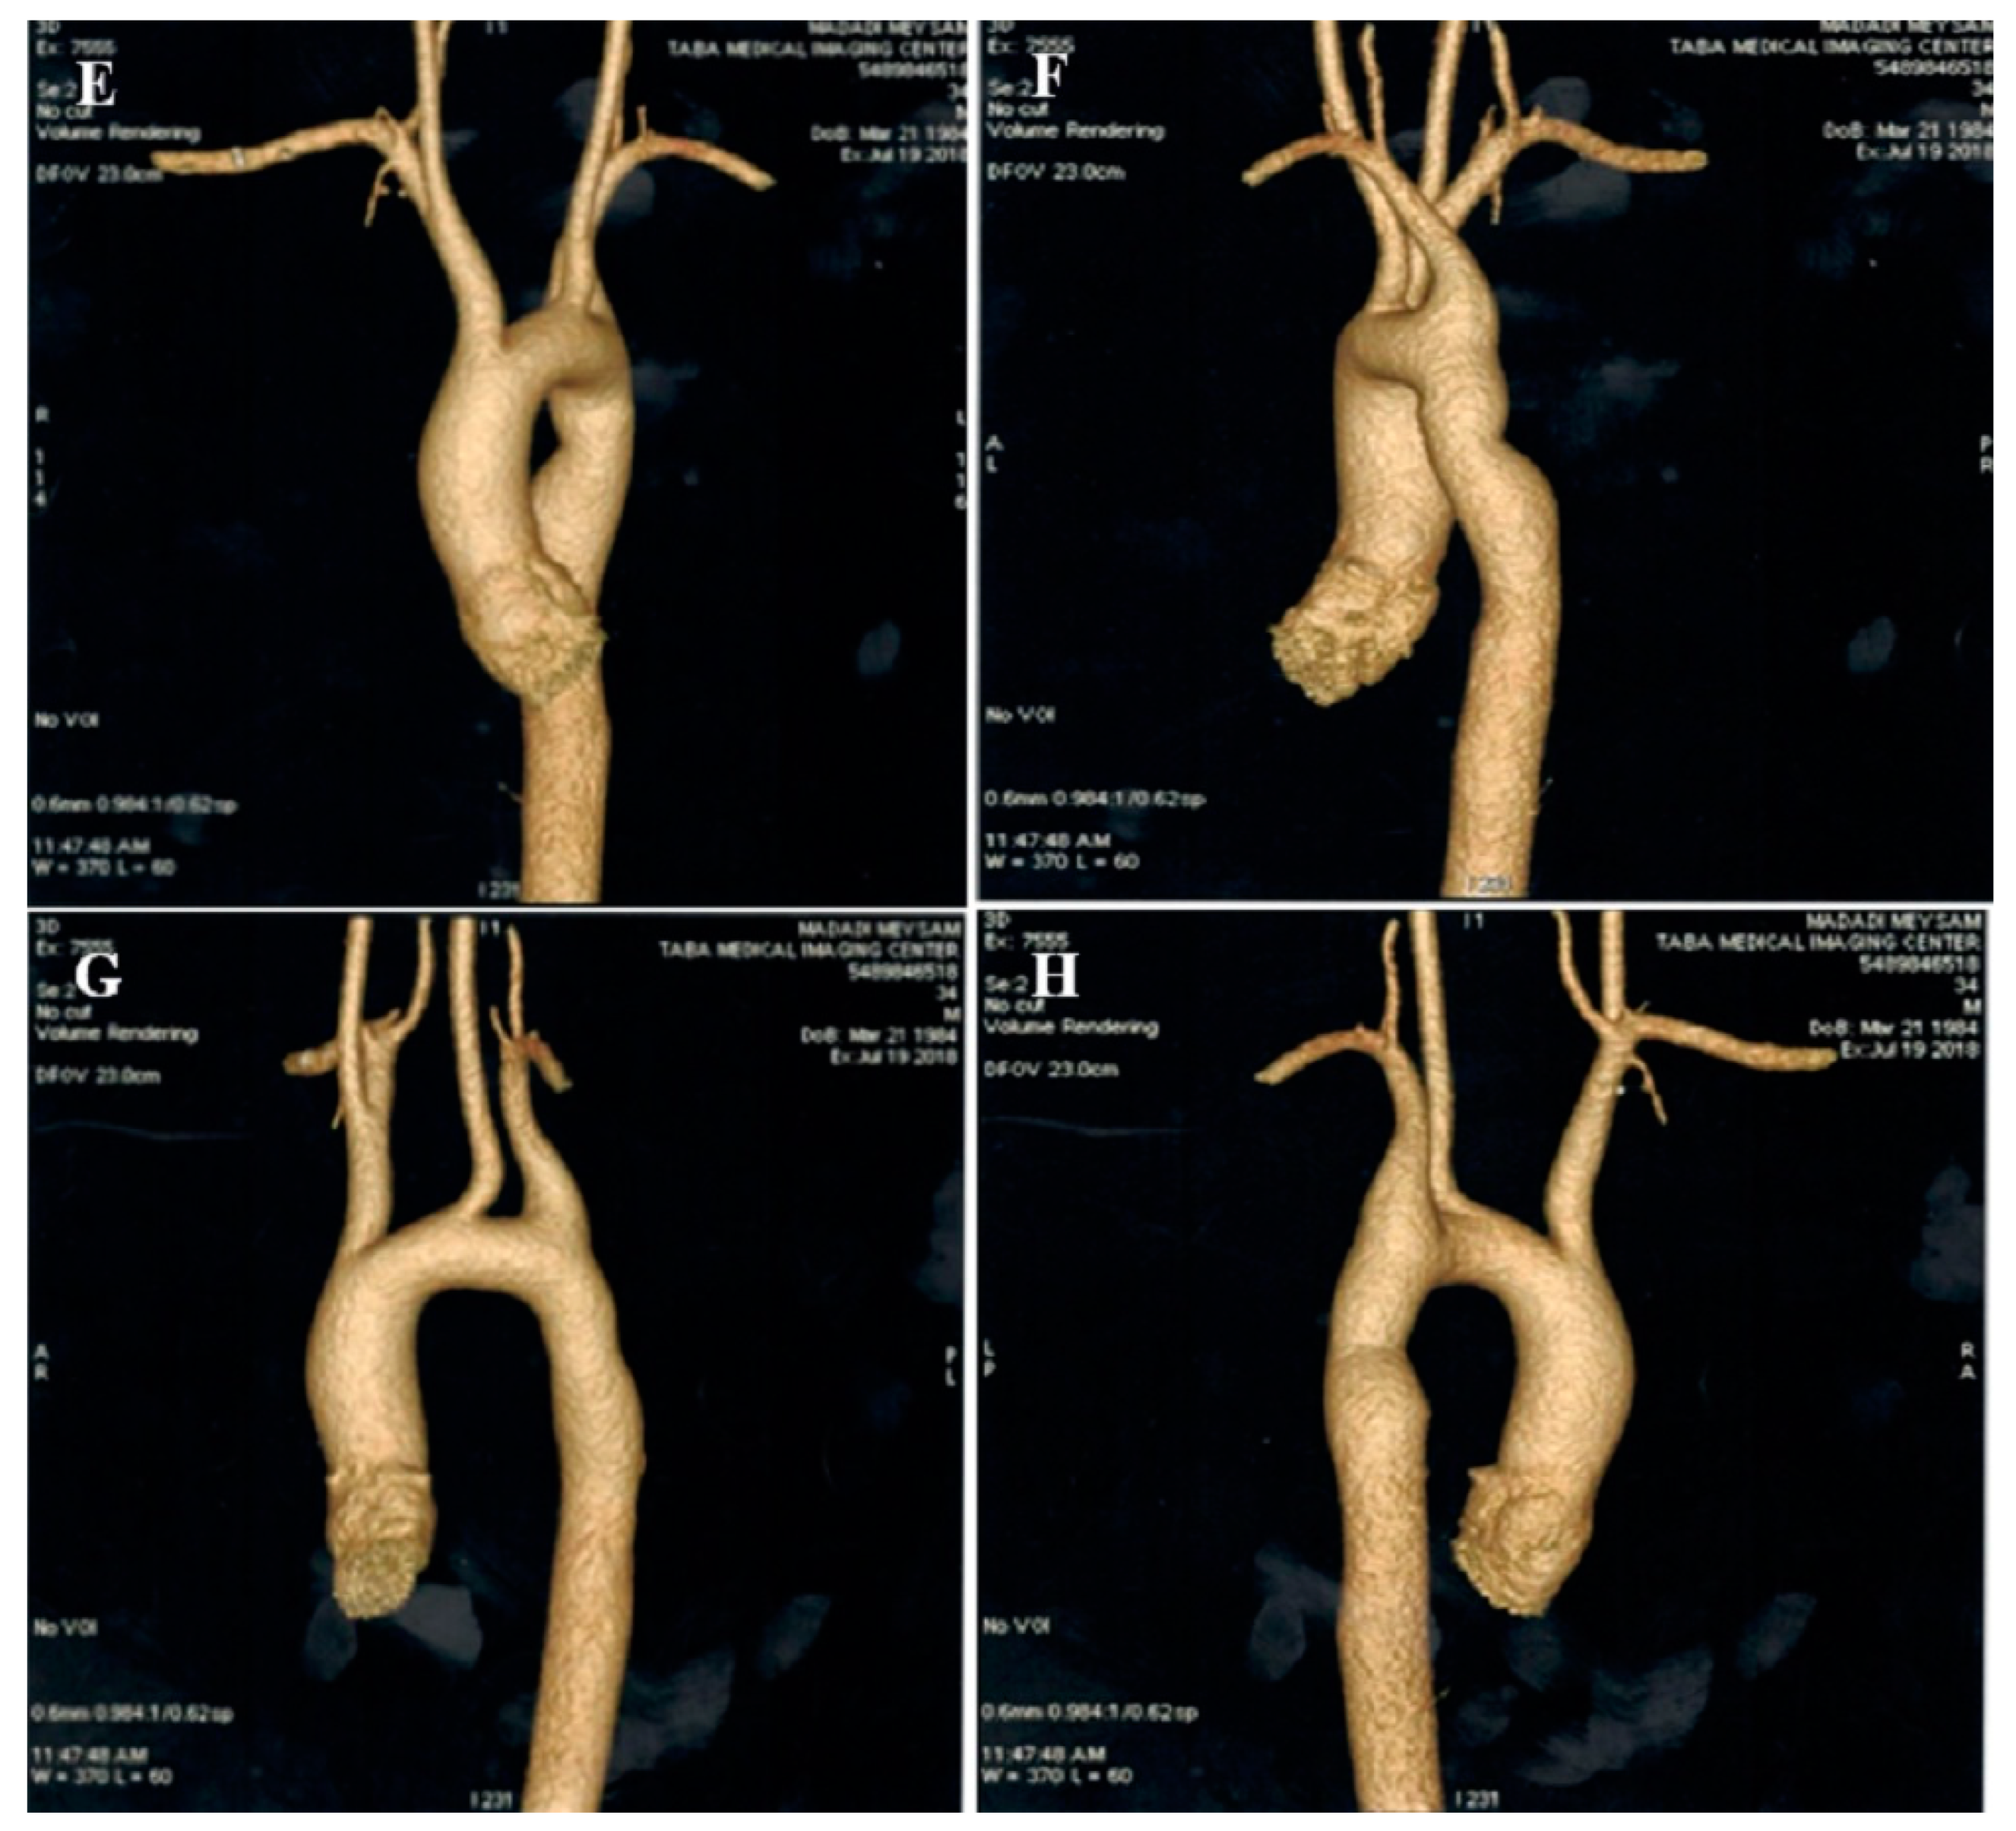

2.2. Case #2. NCLV, Patent Foramen Ovale (PFO), and Fast-Growing Aortic Aneurysm

| 2 | M | 56 | Progressive dyspnea | − | NCLV, LVEF = 16%, Global hypokinesia | Hypoplasia of ascending and arch of aorta plus dilated main pulmonary artery | + | − | Scheduled for a valve-sparing aortic root replacement surgery + post-op carvedilol 6.25 mg TID, furosemide 40 mg daily plus spironolactone 25 mg daily | Doing well |